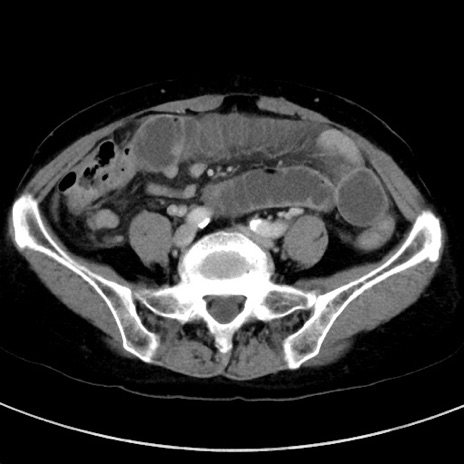

症例23(横断像)

【症例】70歳代女性

【主訴】下腹部痛・嘔吐

【現病歴】2日前より腹痛あり。昨日嘔吐あり。症状改善しないため来院。

【既往歴】胃GISTに対して胃部分切除後。

【身体所見】BT 37.1℃、BP 128/77mmHg、腹部:平坦・軟、下腹部に圧痛あり。

【データ】WBC 10200、CRP 0.31